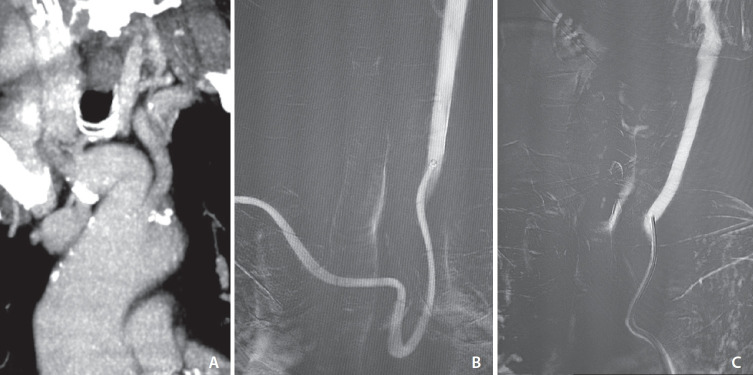

Materials and methods: From November 2022 to November 2023, 22 patients underwent TRA-MT for anterior circulation LVOs, both as first-line and rescue from transfemoral approach (TFA) failure, with the same triaxial setup consisting of a 7F introducer sheath, 7F guide catheter, and aspiration catheters ranging from 5.5F to 5F in relation to the occlusion site. Choice of thrombectomy technique was at operator discretion. Patients' demographic data, clinical presentation, treatment details, complications, rate of crossover to TFA, successful revascularization (modified thrombolysis in cerebral infarction [mTICI] score ≥2b), and good clinical outcome at 3 months (modified Rankin scale [mRS] 0-2) were reported.

Abstract Image